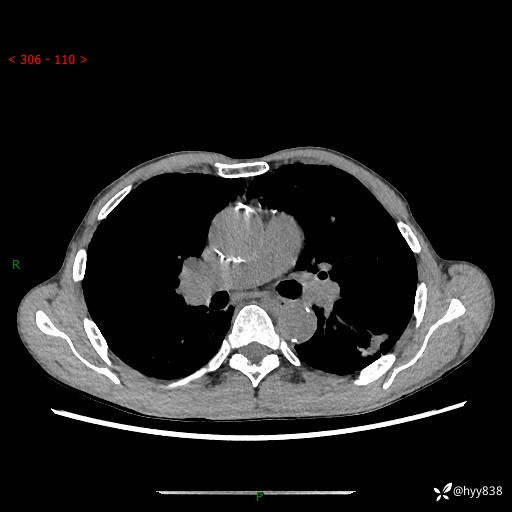

73岁/男,发现肺占位1月余。肺气肿背景,是否恶性倾向---结果公布~

现病史:患者于1月余前无明显诱因出现背部疼痛不适,无明显咳嗽、咳痰、胸闷、咯血、发热等不适,后于2024.5.3至当地市人民医院行胸部CT示:左肺下叶结块,大小约2.2cm*2.6cm,双肺多发小结节,双肺感染性病变,部分纤维增值灶,慢支并双肺局限性肺气肿,肺大泡,纵隔淋巴结增大并部分钙化,冠脉区及大血管壁钙化,双侧胸膜局限性增厚;后口服莫西沙星2周。2024.6.12复查胸部CT示:左肺下叶结块影形态较前饱满,较大截面范围约2.8cm*2.3cm,边缘可见细短毛刺及分叶,性质待查。现患者为求进一步诊治来我院,门诊以“肺占位”收入我科。 起病来,患者精神、食欲、睡眠尚可,大小便正常,体力体重轻微下降。

胸部CT平扫+增强

各期CT值:48hu 100hu 78hu